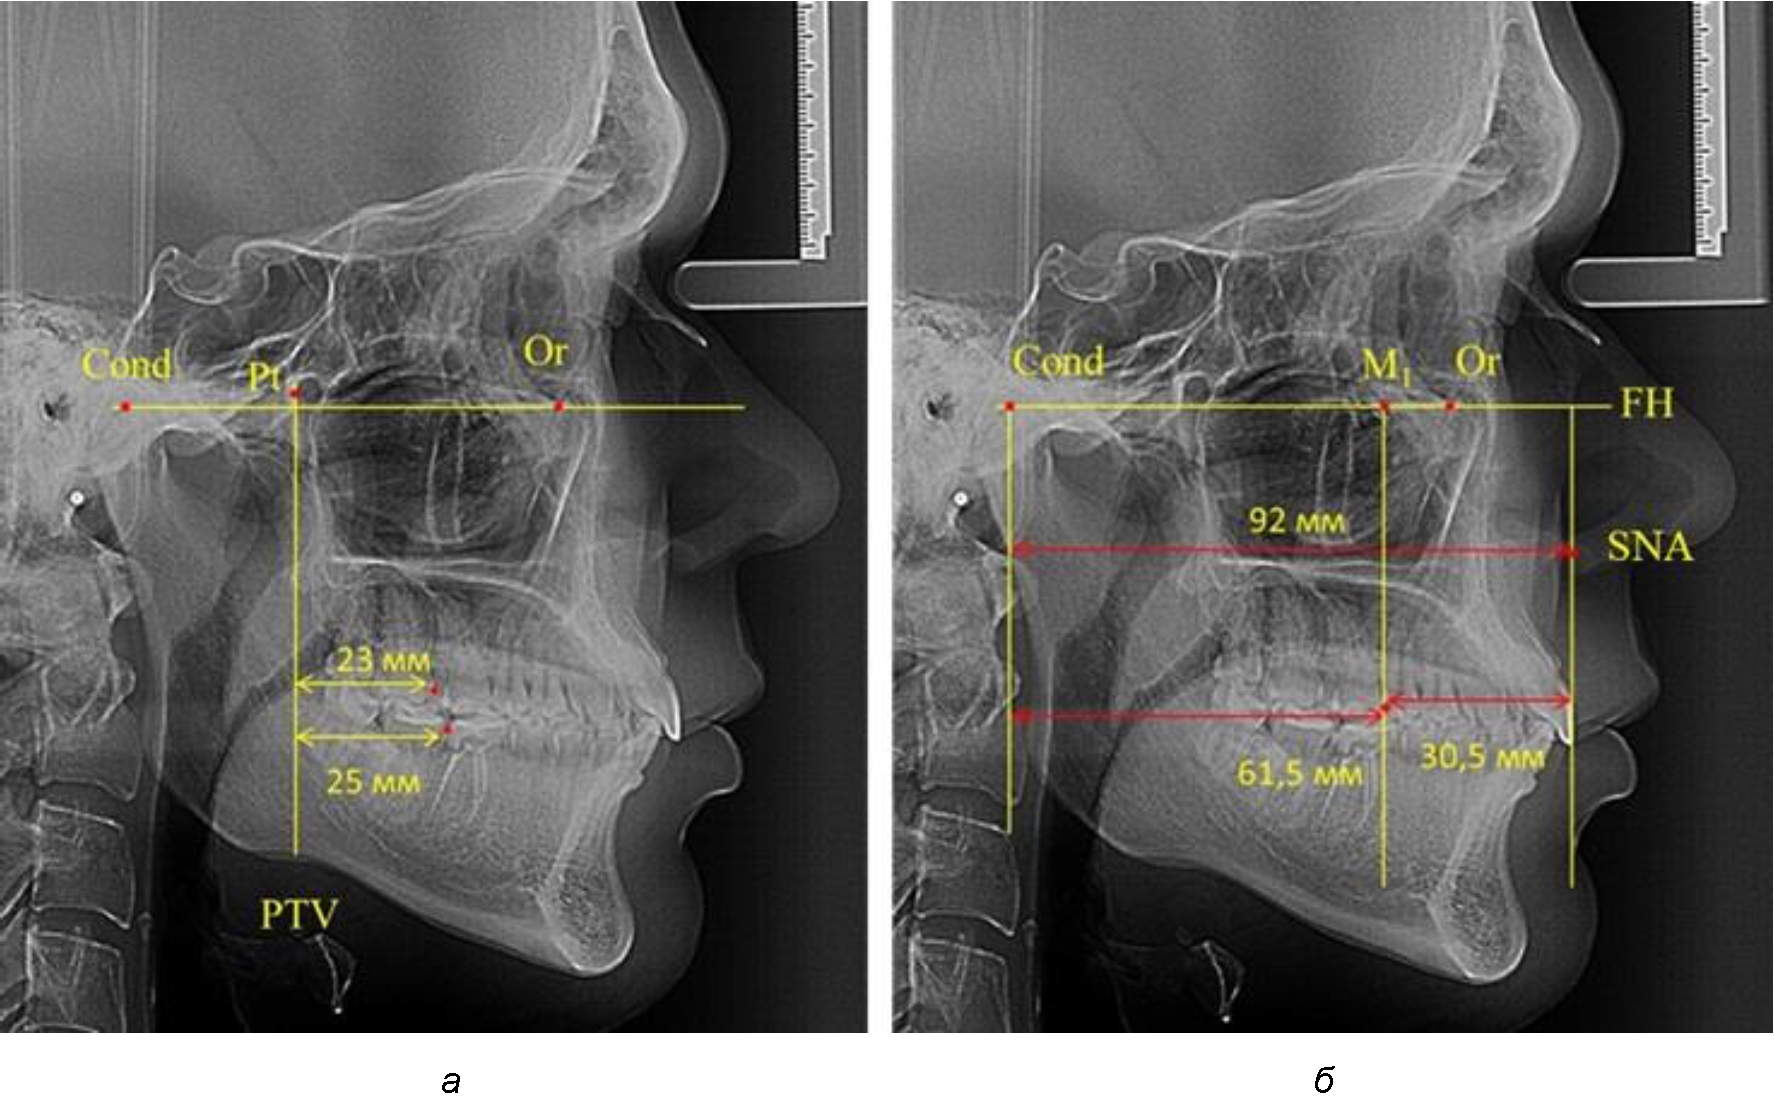

Рис. 1. Метод определения положения первых верхних моляров по Ralph E. McDonald (а) и по предложенному методу (б)

Анализ проведенного исследования рентгенограмм показал существенную вариабельность практически всех линейных показателей. У молодых людей с физиологическим прикусом постоянных зубов расстояние от крыловидной вертикальной плоскости PTV до дистальной поверхности верхнего первого постоянного моляра в целом по группе составляло (18,37 ± 3,62) мм. Обращает на себя внимание большая ошибка репрезентативности из-за разницы между максимальными и минимальными значениями.

Среди анализируемых рентгенограмм минимальное значение расстояния по методу R. E. McDonald было 12 мм, а максимальное достигало 25 мм, что, по нашему мнению, обусловлено вариабельностью сагиттального размера гнатического отдела лица.

Таким образом, для прогнозирования оптимального положения первых постоянных моляров наиболее целесообразным методом явилось использование относительного показателя, что подтверждено при анализе рентгенограмм с минимальными и максимальными значениями по методу R. E. McDonald.

Так, при расстоянии от крыловидной вертикальной плоскости PTV до дистальной поверхности верхнего первого постоянного моляра в 13 мм сагиттальный размер гнатического отдела был 82 мм. При этом отношение кондилярно-спинального расстояния к кондилярно-молярному размеру (54,5) было близким к коэффициенту 1,5, что представлено на рис. 2.

В то же время при увеличенном расстоянии от крыловидной вертикальной плоскости PTV до дистальной поверхности верхнего первого постоянного моляра, равное 23 мм, сагиттальный размер гнатического отдела составил 92 мм. При этом отношение кондилярно-спинального расстояния к кондилярно-молярному размеру (30,5), так же, как и при малых размерах, было близким к коэффициенту 1,5, что представлено на рис. 3.